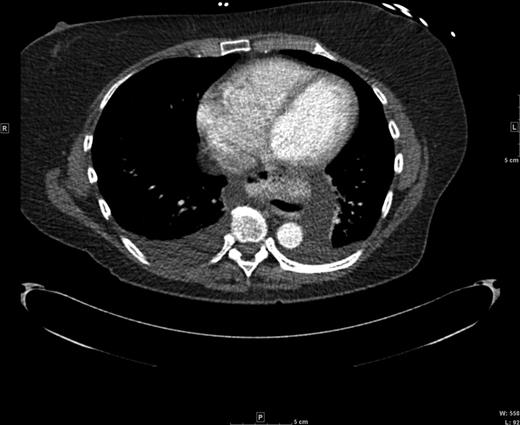

A 60-year-old female with a long-standing gastroesophageal reflux disease and known type III paraesophageal hernia presented to the emergency department with acute epigastric pain, dysphagia and vomiting. She noted a 1-month history of progressive dysphagia as well. Computed tomography (CT) revealed a large paraesophageal hernia with significant surrounding fluid concerning for incarceration (Figs 1 and 2). Owing to these findings and her discomfort, emergent laparoscopic repair of her paraesophageal hernia was recommended.

Coronal CT view of the paraesophageal hernia and mediastinal fluid.